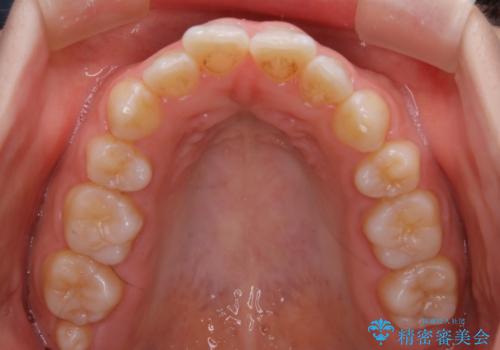

【非抜歯】上下の前歯が噛み合わないオープンバイトの治療

- 噛み合わせの不調を主訴にご来院されました。

骨格的な問題もあり、噛んだ時に奥歯しか当たらず前歯の被蓋があまりない状態でした。

臼歯の位置が高く噛んだ時に奥歯しか当たらなかったり、舌癖などが原因で前歯が前に倒れてしまうことで上下の前歯の被蓋がなくなってしまっている状態をオープンバイトといいます。

前者の場合は臼歯を圧下し沈めてあげることで改善させます。後者の場合は前方に傾斜している歯を元の角度に戻してあげることで改善しますが、舌癖がある場合はその癖自体を無くす治療をしない限りまた同じ状態へと後戻りしてしまいます。